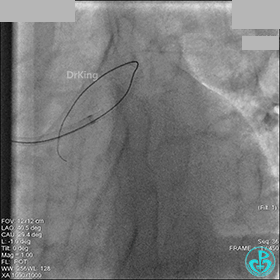

1周后再次上台,右冠脉3级血流,3段局限性严重狭窄,内膜模糊,应该是上次操作夹层遗留下的血肿。

先处理前降支开口严重狭窄并顺利植入前降支到左主干支架。